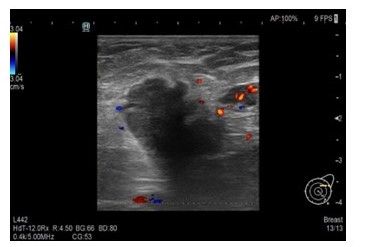

Presentamos el caso de una paciente 53 años, quien consulta refiriendo aumento de volumen en región axilar izquierda de 1 año de evolución. Al examen físico sin evidencia a la palpación de lesiones mamarias, se aprecia en la axila izquierda plastrón ganglionar de 4 cm de diámetro movible, no fijo a estructuras vecinas. En los estudios realizados, como lo son mamografía, eco mamario y resonancia magnética de ambas mamas con gadolinio en marzo 2022, solo se observa, la presencia de lesión de ocupación de espacio en axila izquierda, sugestivo de plastrón ganglionar, sin lesiones subclínicas en las mamas (Figura1,2,3)

Al examen físico mamas grandes asimétricas, presencia de cicatrices de mamoplastia de aumento, portadora de implantes mamarios, no se palpan tumores mamarios, y en la axila izquierda plastrón ganglionar de 4 cm. de diámetro duro movible que no infiltra piel. En vista de los hallazgos clínicos y de imágenes se procedió a realizar biopsia ecoguiada con aguja gruesa de corte, el 11/ 04/ 2022, reportando la anatomía patológica biopsia ap 3542 22, carcinoma ductal invasor grado II, ausencia de componente de carcinoma in situ, desmoplasia acentuada, con resultados para inmunohistoquímica biopsia ap. 3542 22 RE, + RP + ERB 2 neu negativo KI 67: 10 % subtipo molecular intrínseco tipo luminal A (Figura 4).